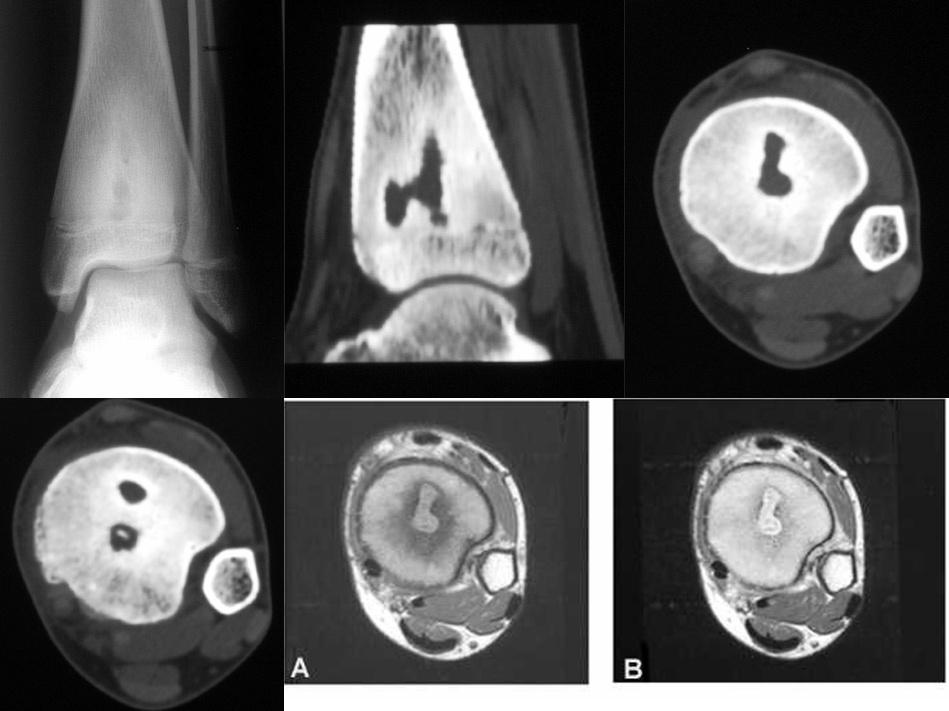

【讨论】胫骨病变(典型病例,影像资料超全,结果已经公布!

ct(直径)